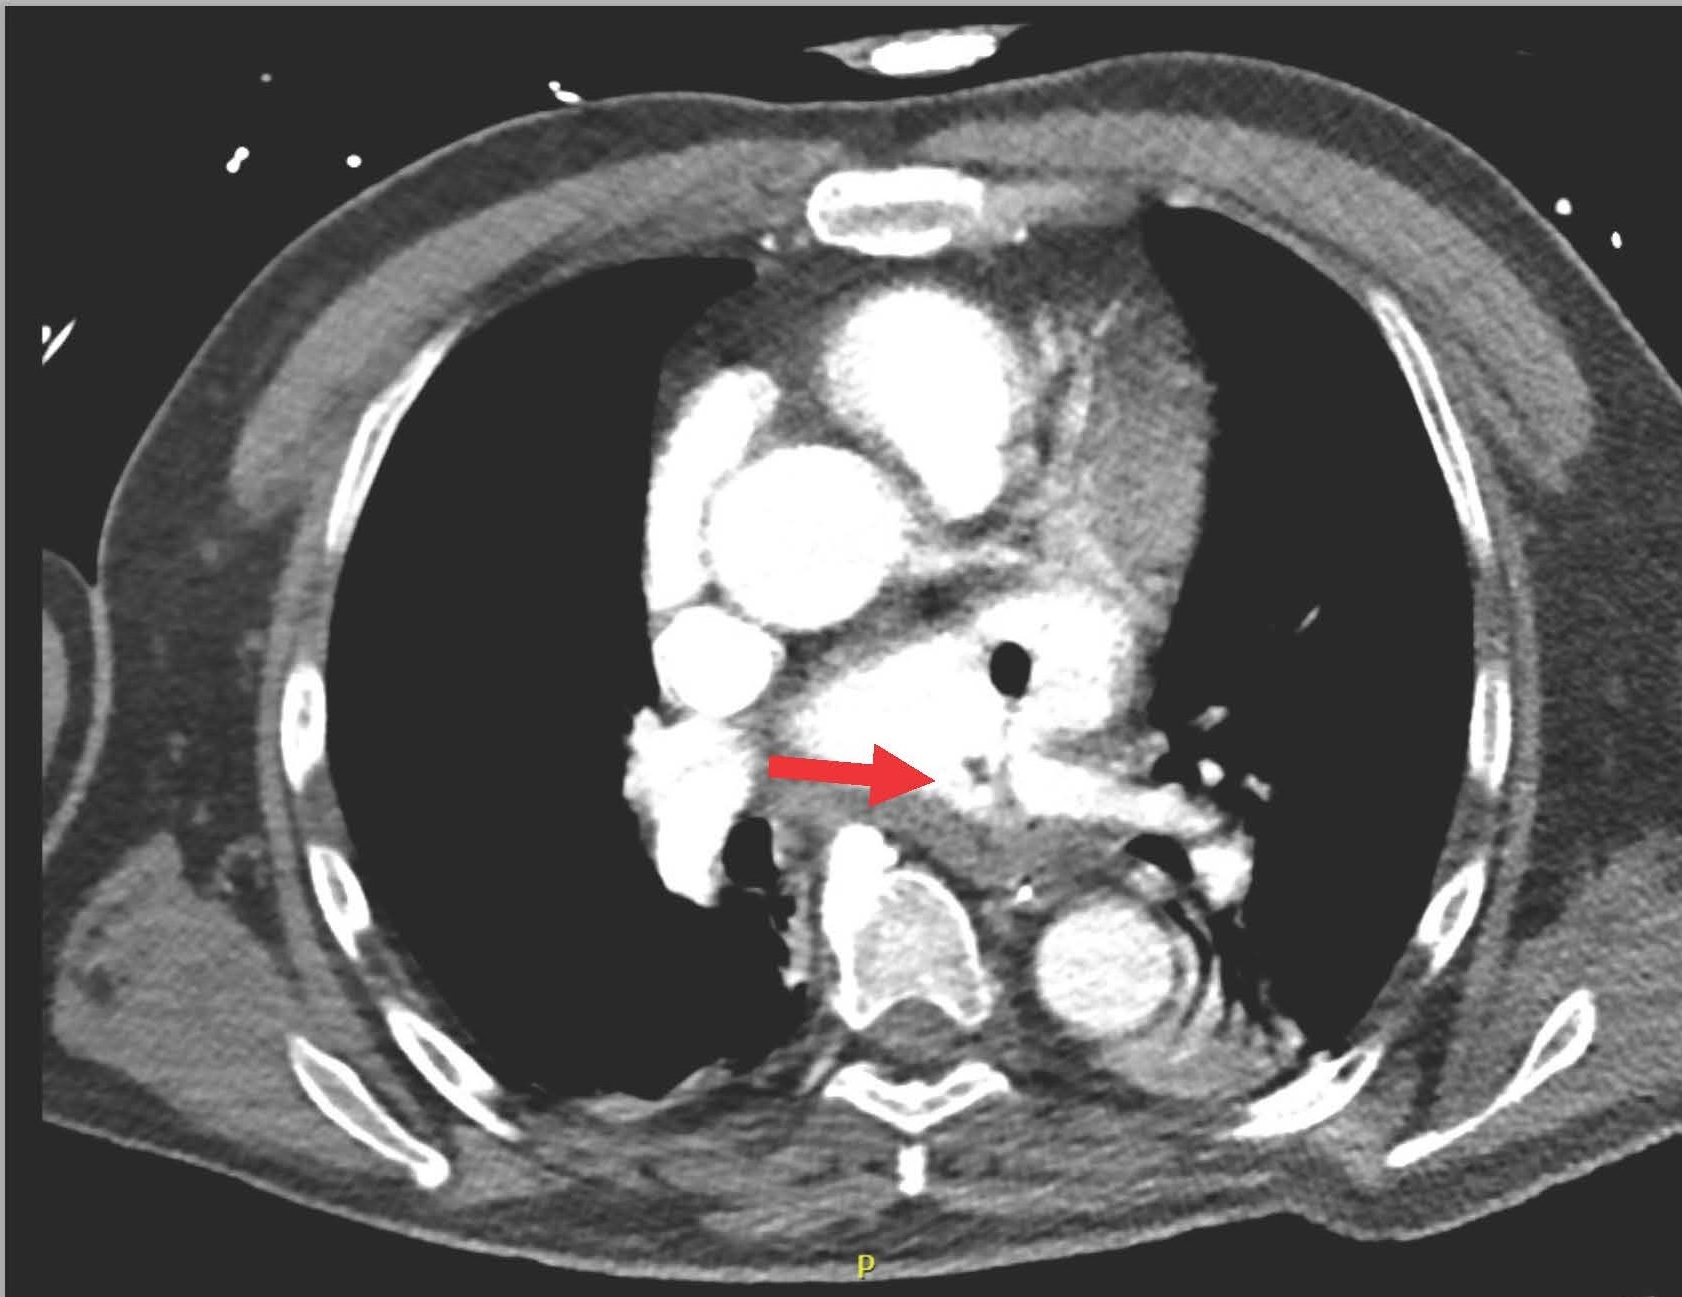

The next day (25 days post-ablation), the patient experienced significant neurological deterioration, with a GCS score dropping to 3/15, supraventricular tachycardia at 122 beats per minute, severe hypotension, and tachypnea with a respiratory rate of 36 per minute. A purpuric rash appeared on the neck, chest, and shoulders, and the patient was febrile with a temperature of 40°C. Due to the severe neurological and septic presentation, he was admitted to the ICU, intubated, and placed on mechanical ventilation. Invasive monitoring and hemodynamic support were initiated. Blood tests showed a marked increase in C-reactive protein (210 mg/L), a white blood cell count of 7.16 x 10^3/µL (65% neutrophils), and significant renal function deterioration. First blood cultures identified multisensitive Streptococcus salivarius, leading to the initiation of antibiotic therapy with amikacin and ceftriaxone for suspected endocarditis. The lumbar puncture was sterile. Transesophageal echocardiography (TEE) later revealed a highly echogenic mass attached to the left pulmonary vein's ostium (Figure 1), severe left ventricular dysfunction, and air bubbles in cardiac cavities (Figure 2). A contrast-enhanced thoracic CT scan showed air in the left atrium and findings consistent with mediastinitis (Figure 3).

Figure 3. Air present in the left atrium and communication between esophagus and LA.